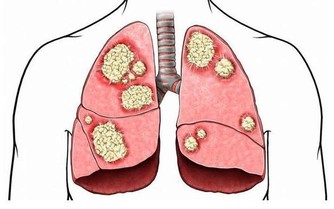

丑時肝經最旺,丑時(1:00—3:00)不眠,肝無法解除掉有毒之物,產生新鮮血液,因藏血不利,面呈青色,久之易患各類肝病。乙肝病毒攜帶者,是由於晚上經常不睡覺,人太虛弱了,也就是說秩序太亂了,病毒已經到了細胞裡了。

肝主疏洩,過子時不睡,可引起肝疏洩不利,肝氣鬱結,可見易怒,頭痛頭暈,眼紅,眼痛,耳鳴,耳聾,胸肋脹痛,女性月經不調,便秘,也可引起肝氣升發不足,人會目倦神疲,腰膝痠軟,暈眩,失眠,驚悸,精神恍惚,重則會暈倒在大街上,不省人事。

肝開竅於目,過子時不睡,易引起肝虛,則出現視力模糊、老花、夜盲、畏光、迎風流淚,等症狀,還會形成青光眼、白內障、眼底動脈硬化、視網膜病變等眼疾。

肝主筋,其華在爪,過子時不睡覺,會引起肝血不足,就出現筋痛,麻木,屈伸困難,痙攣抽搐,易造成灰指甲,缺鈣,髕骨軟化,癲癇病,骨質疏鬆等症。

肝與心,過子時不睡覺,可引起肝血不足,由於心主一身之血脈,肝有儲藏和調節血液的功能,會造成心臟供血不足,引起心慌、心顫等症狀,嚴重的形成心臟病、高血壓等心腦血管疾病。

三、睡眠的方法

如果你每晚22點鐘左右躺下,靜靜得不要說話,到23點的時候,也就睡著了。肝膽開始回血,把有毒的血過濾掉,產生新鮮的血液,到一百歲也沒有膽結石,也沒有肝炎、囊腫一類的病。如果你天天熬夜到1點多,肝回不了血,有毒的血排不掉,新鮮的血生不成,膽又無法換膽汁,所以這些人容易得膽結石、囊腫、大三陽、小三陽各種病症。